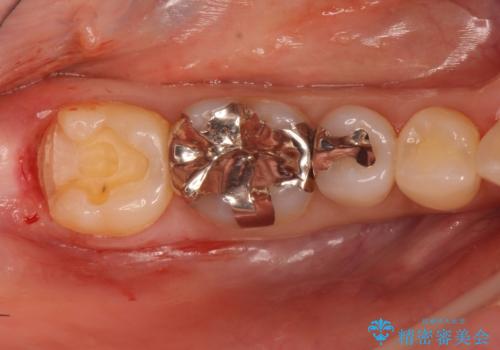

- 詰め物が外れたから作り直しをしたいとのことで来院されました。

外れた状態で日にちが経過していたため、まわりの歯ぐきが歯の上に乗っかっている状態です。

歯ぐきの形を整えてから治療をしていきます。

歯ぐきの形を整えることで精度の良い詰め物を入れることができました。